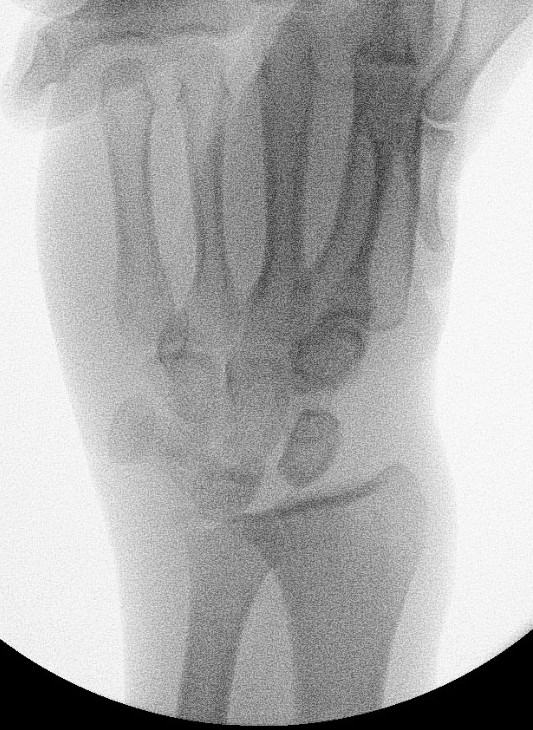

Xray

Dorsal radiocarpal dislocation with dorsal rim fracture

Dorsal radiocarpal dislocation with radial styloid fracture